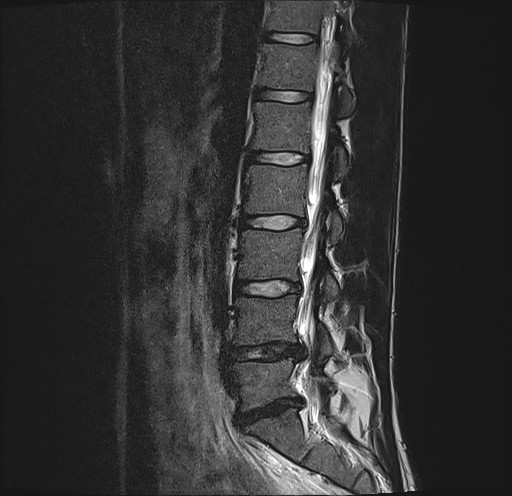

That's what I've been thinking too for the past years but despite trying 8 physios and focusing on hinge and flexion it keeps getting worse. It's like my spine doesn't care what I do. Before at least I could still hope to get better but now I can't sleep without painkillers and my dick and balls are giving up. For reference my chud lumbar.

I also hate the idea of getting surgery it's terrifying but all my movement rehab efforts were just punished by my back, even the mcguill big 3 manage to piss off my back